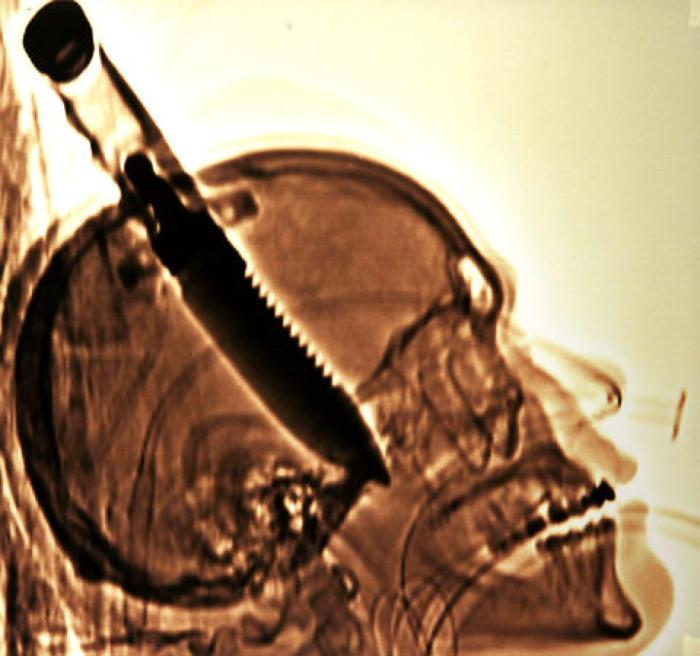

craziest x rays 16

700x656 (48.55 KiB)